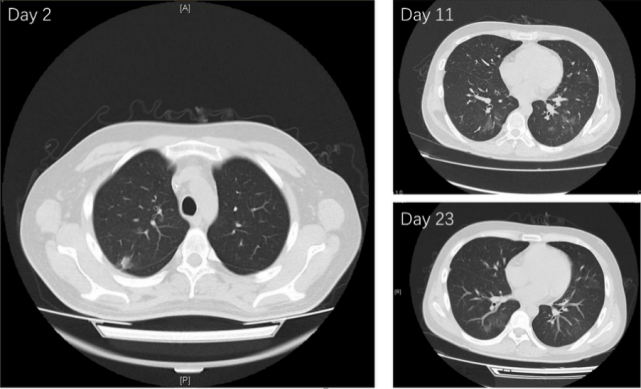

图片

图4 患者入院第2天、第11天及第23天肺部CT结果(第23天肺部CT结果显示阴影较前有所吸收)

但入院后第十六天,患者痰培养检出头孢他啶-阿维巴坦敏感CRKP(命名为HS02),药敏结果显示该细菌对头孢他啶-阿维巴坦、替加环素敏感,对亚胺培南、美罗培南、多黏菌素等耐药(图3)。NG-testCarba5检测结果显示KPC阳性,该细菌携带KPC型碳青霉烯酶。随即使用PCR及测序发现,HS02携带blaKPC-2。考虑患者体内不排除同时存在KPC-2阳性、KPC-33阳性肺炎克雷伯菌的感染,故再次调整抗感染方案,方案更改为头孢他啶/阿维巴坦2.5gq8h联合亚胺培南1gq8h。随后患者临床症状明显改善,咳嗽咳痰改善。第21天及第23天痰培养均未检出肺炎克雷伯菌,肺部CT显示阴影较前有所吸收,入院后第23天患者结束该阶段抗感染治疗,好转出院。